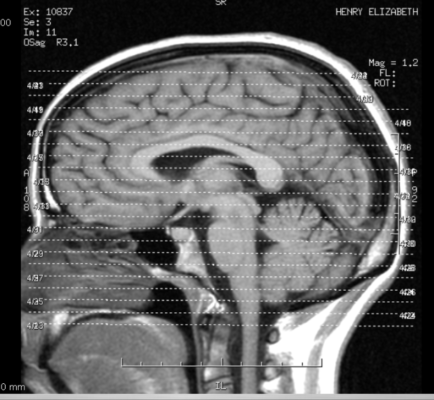

Head Injuries: What Actually Happens To Your Brain

my brains – let me show you them by Liz Henry / CC BY-ND 2.0